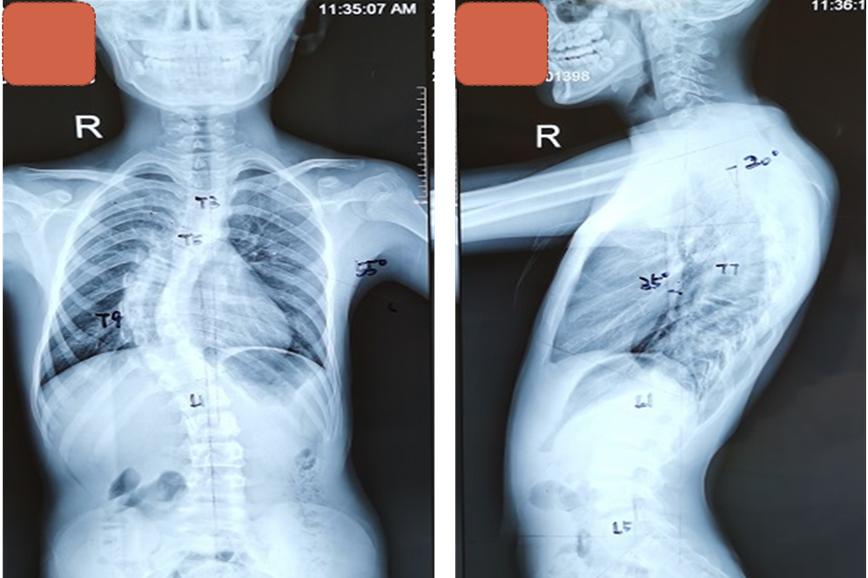

术前X线患者胸椎55度侧弯

手术中,团队密切配合,采取胸腰椎后入路固定手术,同时在5个节段的脊柱进行截骨,通过直接去旋转技术,将少年高达55度的脊柱侧弯进行全面矫正。保证矫正效果,降低内固定节段过多带来的并发症。“我们还为患儿实行了皮内缝合,伤口无需拆线,孩子身体外观几乎看不出来大手术的痕迹”夏主任说。